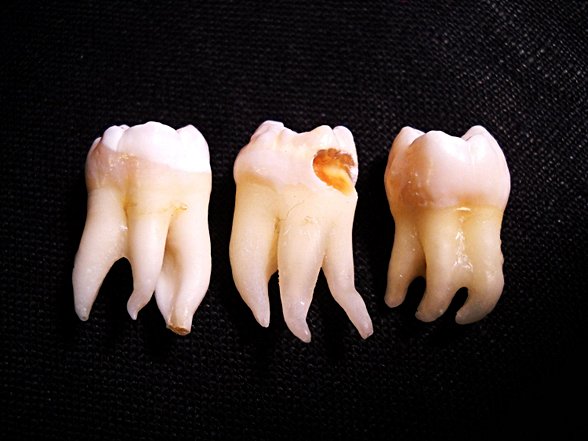

Yirmi yaş dişlerinin sıklıkla gömülü kalırlar, çıktıkları zaman doğru şekilde çıkmazlar ve diğer dişlere sürtünerek onların yapısını bozabilirler. Bu nedenle de ağrı ve enfeksiyona neden oldukları bilinmektedir. Bunun haricinde ise hiçbir işlevleri bulunmamaktadır. Dolayısıyla ağrıya neden oldukları zaman, diş hekimleri tarafından çekilerek hasta rahatlatılabilmektedir. 20 yaş dişleri çekilen kişilerin ağız fonksiyonlarında hiçbir azalma olmamaktadır. Aşağıda bu dişleri görmektesiniz: